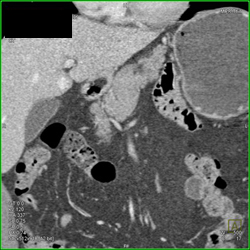

Catheter From Stomach Into Pseudocyst